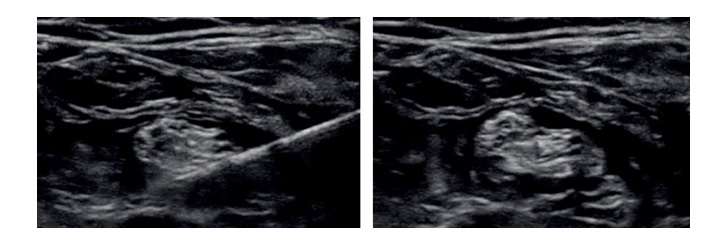

Poniżej na zdjęciach przedstawiono obraz sonoanatomiczny blokady nerwu obwodowego. Wskaż sytuację kliniczną, w której zastosowanie tej blokady będzie najbardziej uzasadnione: